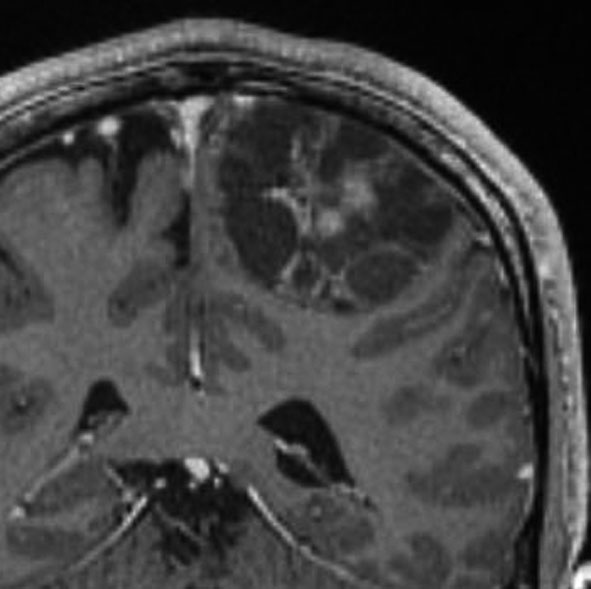

成人の大脳皮質のう胞性毛様粘液性星細胞腫

症候性てんかんで発症した30代の毛様粘液性星細胞腫です。術前診断で,のう胞性髄膜腫 cystic meningioma と間違えました。腫瘍内でごくわずかに出血していました。毛様細胞性星細胞腫は腫瘍内出血をしばしば生じます。実質部分はガドリニウム増強されていて多房性のう胞があります。成人型の毛様粘液性星細胞腫としては全く矛盾のない画像なのですが,発生した部位が頭頂葉皮質だったので術前診断できませんでした。eroquent areaなので完全摘出する必要はありません,のう胞壁を取り残しても再燃しません。